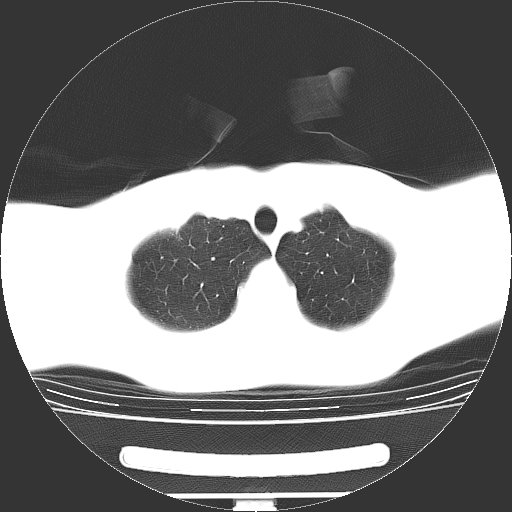

标题: CT19767:男,20岁,右侧气胸行闭式引流术后五天CT检查。 [打印本页]

标题: CT19767:男,20岁,右侧气胸行闭式引流术后五天CT检查。

男,20岁,右侧气胸行闭式引流术后五天ct检查看肺内是否有肺大泡,纵隔窗未见异常,未上传。

未见肺大泡影

右肺未见确切肺大泡。

1)右侧胸腔闭式引流术后导管留置。2)右肺未见肺大泡。

未见肺大泡,还有微量气体。